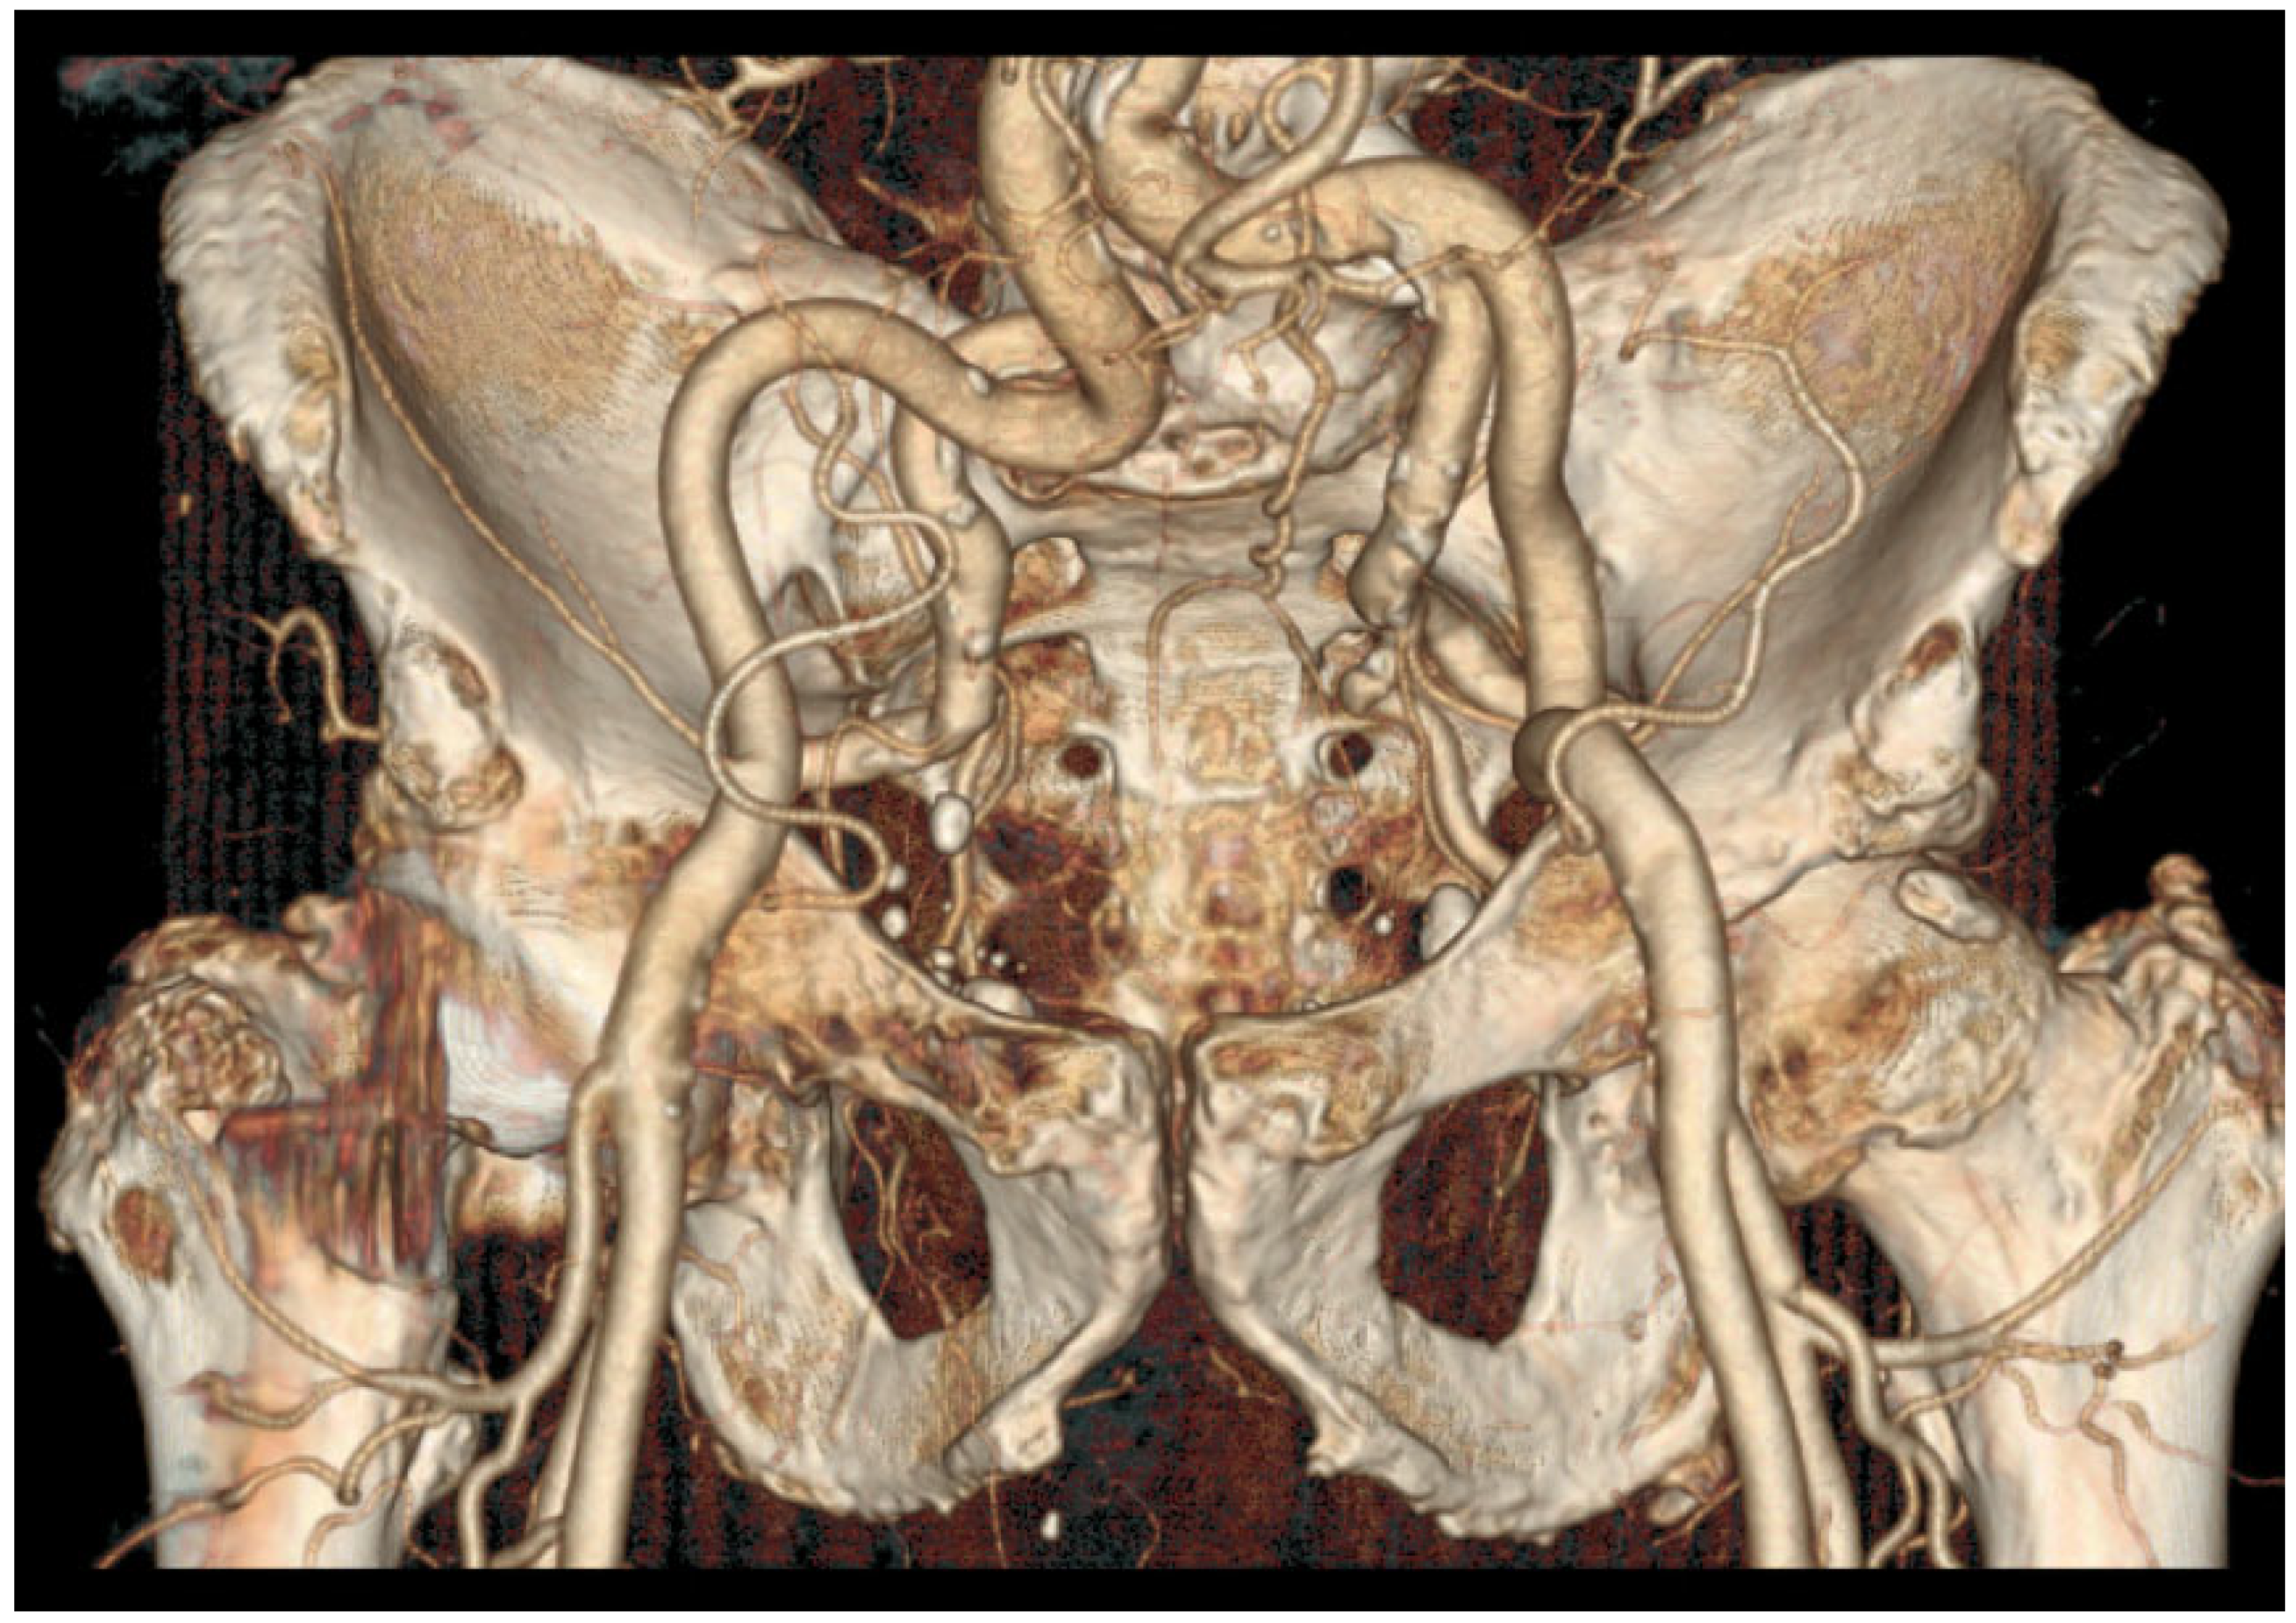

- Tortuous common iliac arteries (Figure 1);

Figure 1. A CT scan with a 3D reconstruction showing very tortuous iliac arteries and very acute right internal/external iliac angulation. Upper radial access was privileged in the first intention. - Aortic or iliac bifurcation forming a very acute angle.